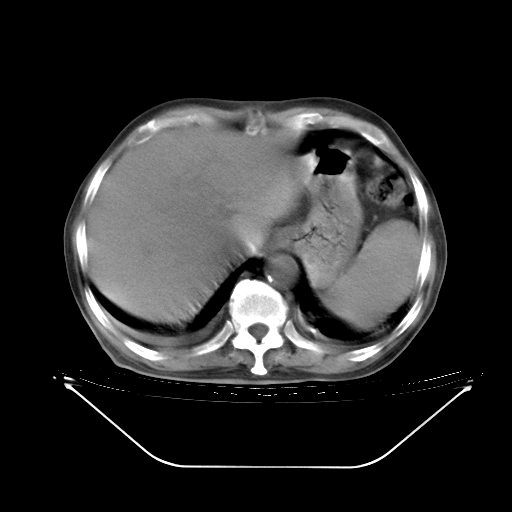

胸腹部CT,诊断意见:左上肺叶钙化灶、左侧胸膜局限性增厚并钙化、胆囊炎。描述部分肺组织呈磨玻璃样改变。

今天复查肺部CT,发现双肺广泛磨玻璃样改变。所以我把3月19日和5月9日相隔50天的肺部CT上传。请大家会诊。

5月9日肺部CT(在4月27日齐鲁医院肺部CT描述部分肺组织磨玻璃样改变,12天后肺组织广泛磨玻璃样改变)

大致读了系列胸部CT:纵隔窗无明显异常,肺窗:从4、27至今:主要是双肺中下野外带可见毛玻璃样改变,目前处于急性肺泡炎阶段,至于原因考虑1、结替组织或胶原血管性疾病所致?2、恶性疾病如恶组在肺部所致的表现或细支气管肺泡癌?3、药物或其它原因如肺蛋白沉着症所致肺泡炎目前不太可能?总之,明天就去请我院的呼吸科、感染科、血液科和临免专家会诊哈。